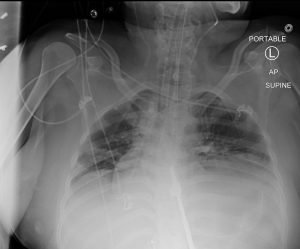

Gastrothorax Post NG Placement XRay. JETem 2017